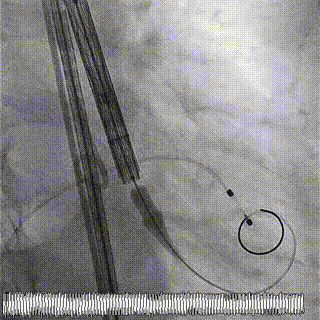

术中影像

1.主动脉根部造影,可见大量反流

2.输送系统过主动脉弓

3.输送系统造影定位

4.释放瓣膜

5.瓣膜完全释放

6.最终造影,反流消失

手术结果

术后食道超声及造影未见瓣周漏,效果良好,手术圆满完成。